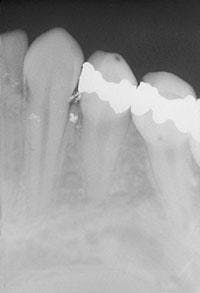

The diagnosis of an amalgam tattoo is based on its suggestive clinical appearance along with radiographic confirmation.

When an amalgam tattoo is suspected, a radiograph of the area should be exposed. The amalgam fragments, embedded in soft tissue or bone, should appear radiopaque on an exposed radiograph (see film).

In some cases, however, there is no radiographic evidence of the amalgam fragments. If no evidence of amalgam is seen on a dental radiograph, and the lesion cannot be diagnosed on a clinical basis, a biopsy should be performed in order to rule out melanocytic neoplasia.